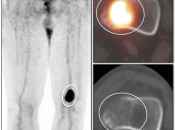

Utility of PET/CT for Known Primary Bone Tumors:

Initial Staging: Permits both assessment of initial disease and serves as a baseline exam for follow up reference.

- Primary lesion: Size, location and metabolic activity.

- Directs Biopsy: Can sample region of greatest metabolic activity.

- Grading: High-grade vs. low-grade determined by metabolic activity (helps guide therapy and correlates with overall prognosis)

- Regional & Distant Disease: Most commonly to the lungs (also to bones, nodes & brain)